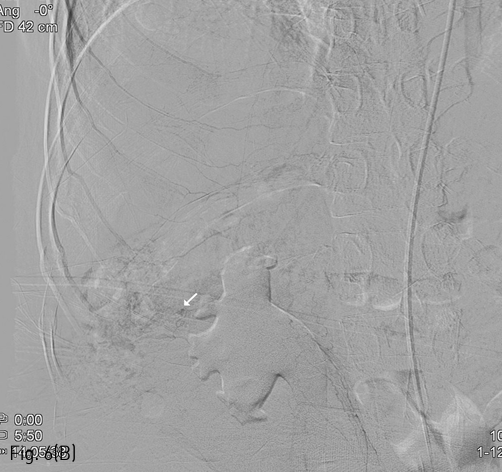

Fig 5B

(B) Pseudoaneurysm formation is noted at previous angiographic catheterization site of the left common femoral artery (black arrow).